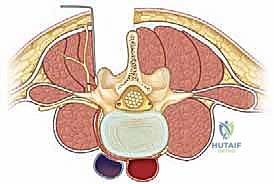

لفهم مدى خطورة الانزلاق الفقاري عالي الدرجة، يجب الغوص في التشريح المعقد للعمود الفقري، وتحديداً المنطقة القطنية والعجزية (Lumbar and Sacral Spine). يتكون العمود الفقري من سلسلة من العظام (الفقرات) المتراصة فوق بعضها البعض بدقة هندسية ربانية، وتفصل بينها أقراص غضروفية (Discs) تعمل كممتصات للصدمات ومسهلات للحركة.

في المنطقة القطنية السفلية، وتحديداً بين الفقرة القطنية الخامسة والفقرة العجزية الأولى (L5-S1)، يقع العبء الأكبر من وزن الجسم والضغط الميكانيكي. يتم الحفاظ على ثبات هذه الفقرات بواسطة مفصلات خلفية (Facet Joints) وجزء عظمي دقيق يُعرف بـ "برزخ القوس الفقري" (Pars Interarticularis). عندما يحدث كسر أو ضعف أو استطالة في هذا البرزخ، تفقد الفقرة دعامتها الخلفية، ومع تأثير الجاذبية ووزن الجسم، تبدأ الفقرة العلوية بالانزلاق للأمام فوق الفقرة السفلية.

في الانزلاق عالي الدرجة، يتجاوز هذا الانزلاق نصف مساحة سطح الفقرة. هذا التحرك الميكانيكي العنيف يؤدي إلى شد وتمزق الأربطة المحيطة، وتدمير القرص الغضروفي، والأخطر من ذلك؛ تضييق الخناق على الحبل الشوكي والأعصاب المتفرعة منه، مما يفسر تنوع وشدة الأعراض التي يعاني منها المريض.

1. تخفيف الضغط العصبي (Decompression / Laminectomy)

الخطوة الأولى والأهم هي إزالة الضغط عن الحبل الشوكي والأعصاب. يتم ذلك من خلال استئصال الصفيحة الفقرية (Laminectomy) وإزالة الأربطة المتضخمة (Ligamentum Flavum) وأي أجزاء من الغضروف المنزلق تضغط على الأعصاب. يتم إجراء هذه الخطوة تحت الميكروسكوب الجراحي لضمان عدم المساس بالأغشية العصبية الرقيقة (Dura Mater). بمجرد تحرير الأعصاب، يزول سبب الألم الجذري (عرق النسا) فوراً.